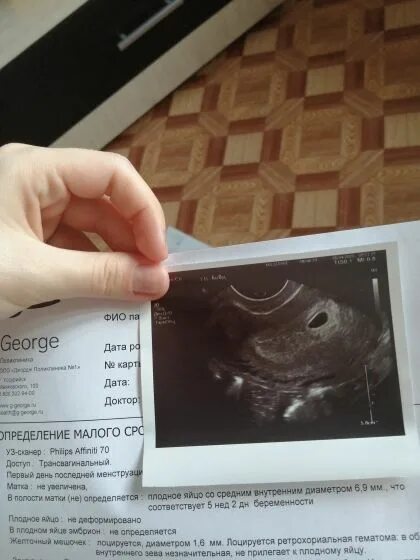

Беременна 2 недели срок